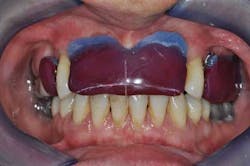

Figs. 3a, b, and c: Extraction of the upper incisors and maxillary removable acrylic placement

- Teeth preparation, impression, and metal framework fabrication for PFM crowns on teeth Nos. 2 and 3.